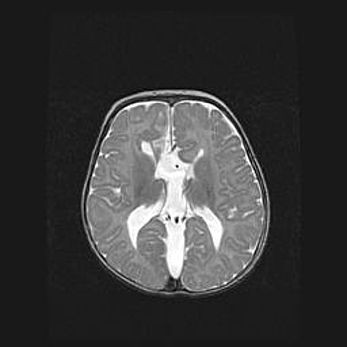

Открытая гидроцефалия.

Возраст: 9 месяцев 12 дней

Вес: 6800 г

Пол: мужской

Окружность головы: 41,5 см

Срок гестации: 28 недель

Гидроцефалия головного мозга у новорожденных имеет характерный признак: опережающий рост окружности головы приводит к визуально хорошо определяемой гидроцефальной форме сильно увеличенного в объёме черепа. Детские неврологи определяют следующие симптомы гидроцефалии у грудничков: выбухающий напряжённый родничок, частое запрокидывание головы, смещение глазных яблок к низу.